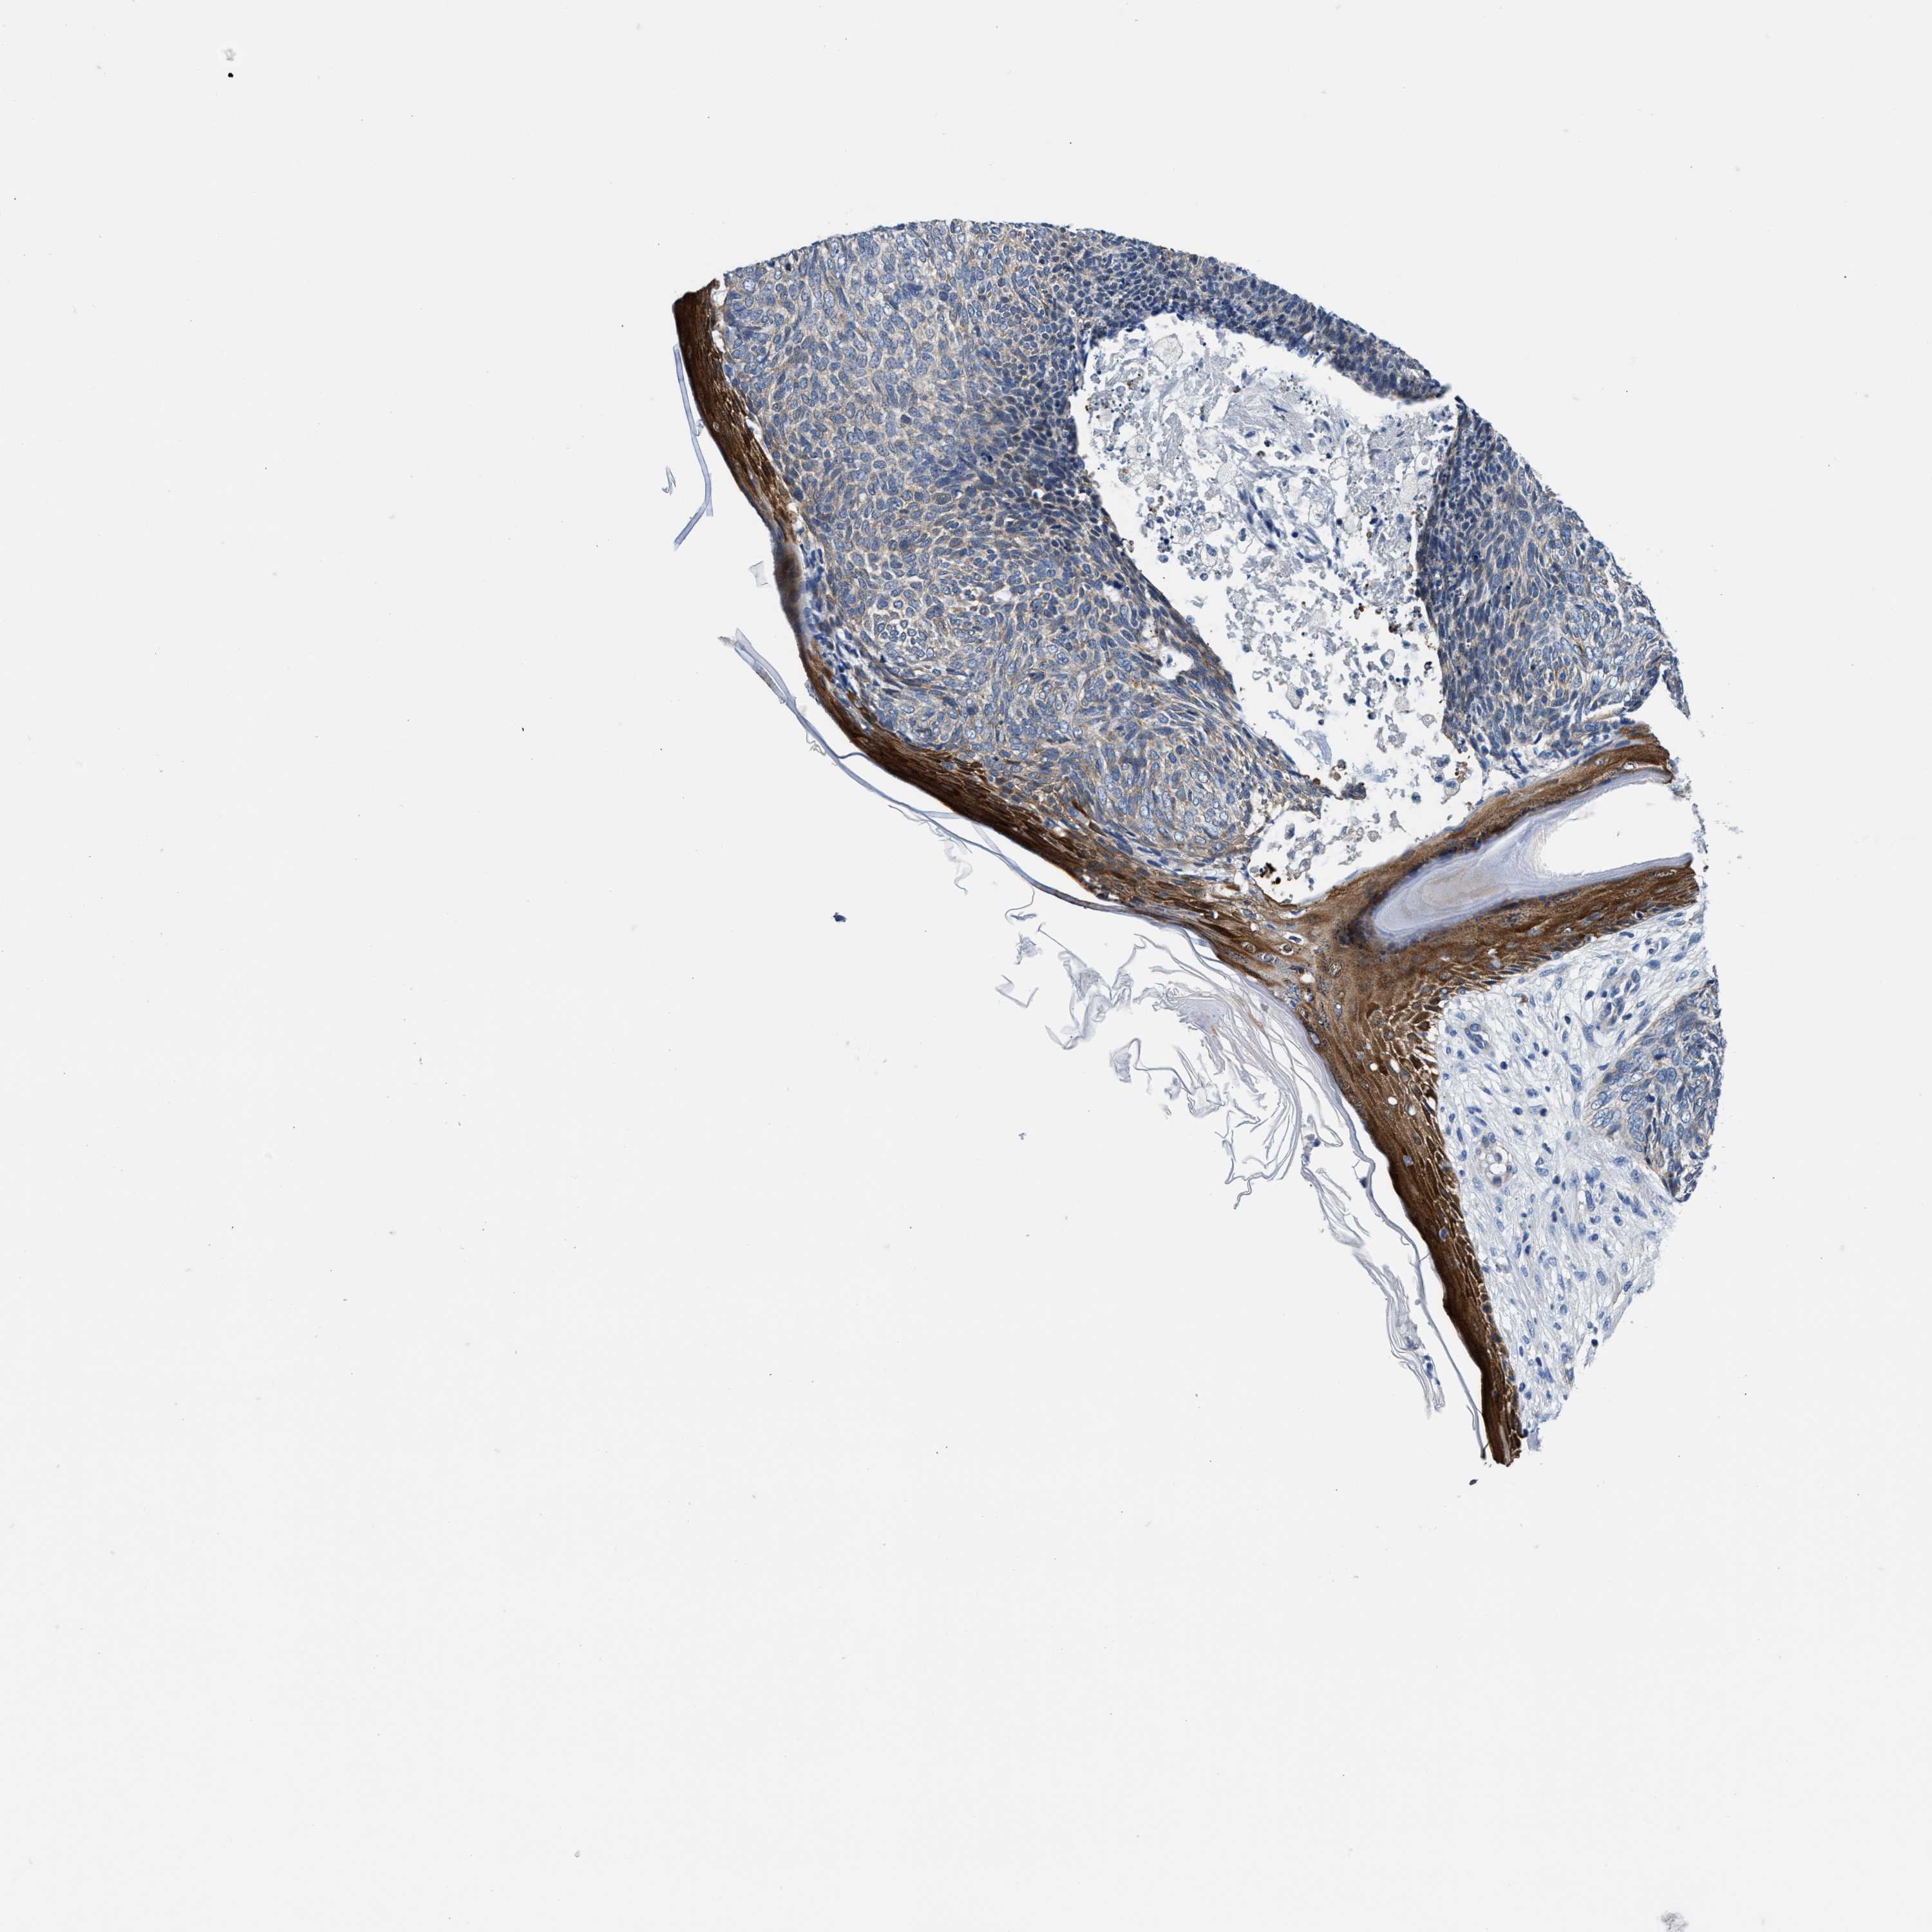

Basal cell and squamous cell cancer

SKIN CANCER - Protein expressioni

A mouse-over function shows sample information and annotation data. Click on an image to view it in a full screen mode. Samples can be filtered based on level of antibody staining by selecting one or several of the following categories: high, medium, low and not detected. The assay and annotation is described here.

Antibody stainingi

Antibody staining in the annotated cell types in the current human tissue is reported as not detected, low, medium, or high, based on conventional immunohistochemistry profiling in selected tissues. This score is based on the combination of the staining intensity and fraction of stained cells.

Each image is clickable and will lead to virtual microscopy that enables deeper exploration of all samples and also displays staining intensity scores, fraction scores and subcellular localization as well as patient and tissue information for each sample.

Antibody HPA021819

Staining

High

Medium

Low

Not detected

Intensity

Strong

Moderate

Weak

Negative

Quantity

>75%

75%-25%

<25%

None

Location

Nuclear

Cytoplasmic/membranous

Cytoplasmic/membranous,nuclear

Squamous cell carcinoma, metastatic, NOS